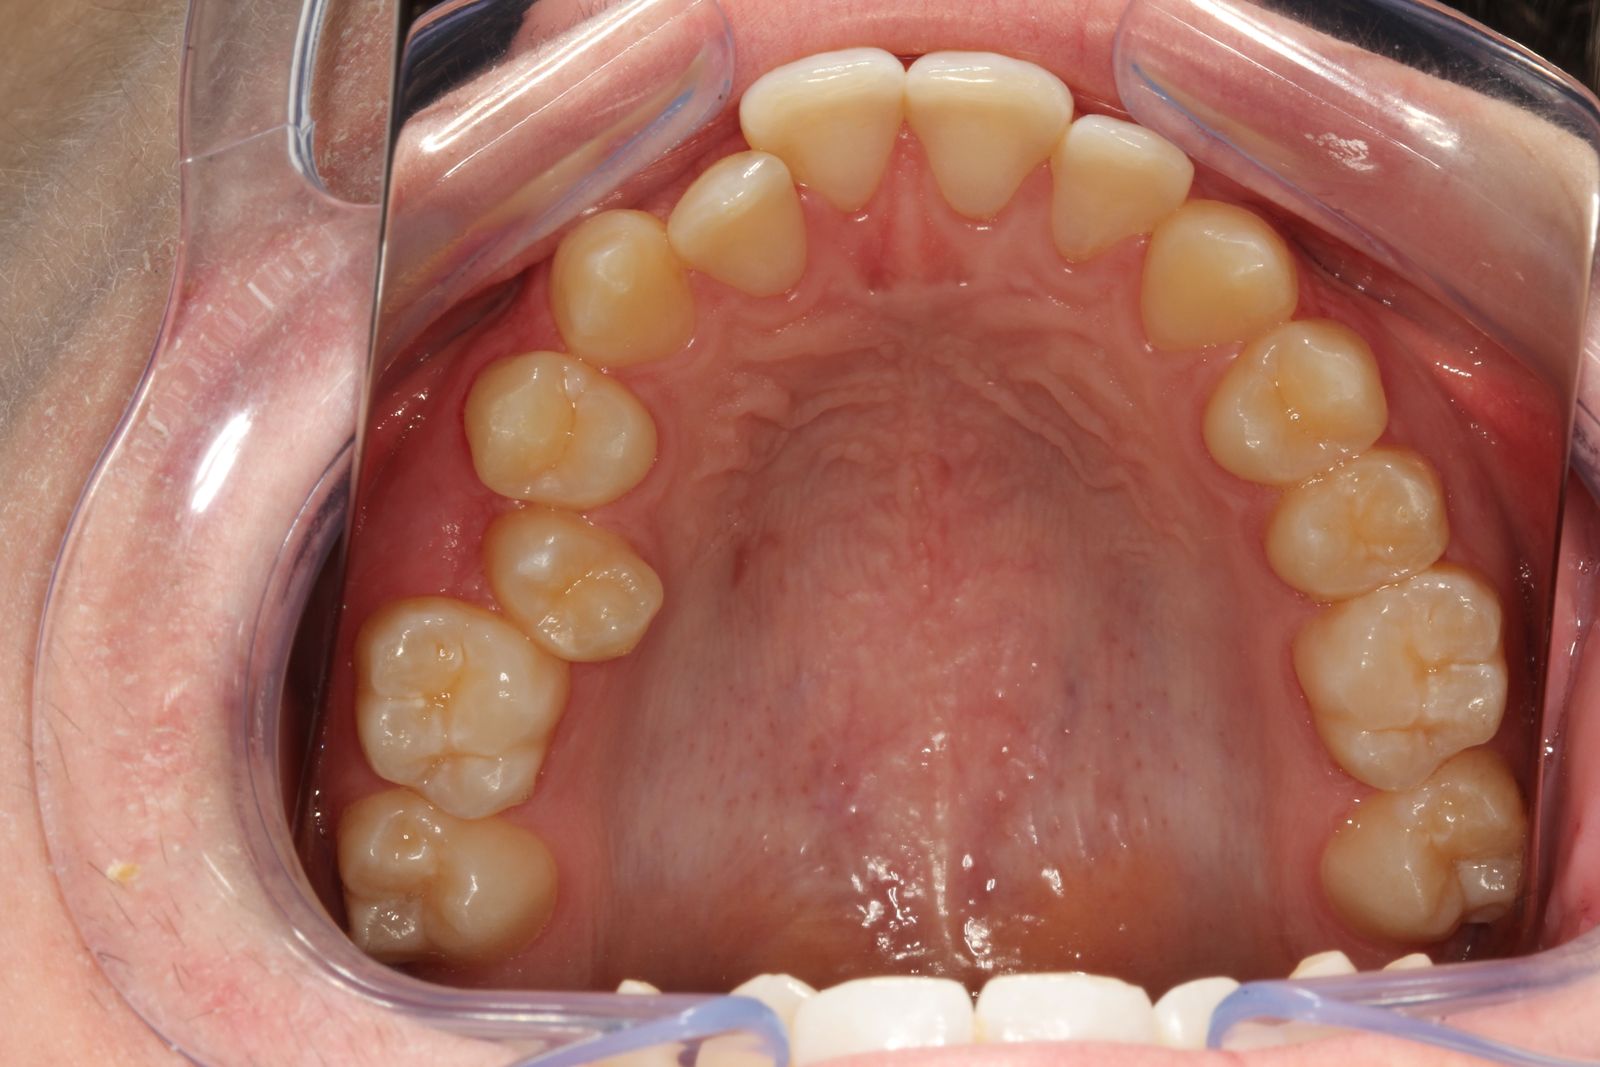

“O início do procedimento é realizado na clínica mesmo, com o escaneamento dos dentes e um pré-planejamento digital de como eles deverão se movimentar ao longo do tratamento”, explica Correia. “A partir desse primeiro momento, é possível visualizar o resultado final antes mesmo de iniciar o uso.”

Após esse planejamento ilustrado no vídeo acima, o dentista envia as informações para o laboratório responsável pela confecção das placas. Cada conjunto de alinhadores é trocado periodicamente, seguindo a evolução dos dentes até atingir o alinhamento ideal.

Os alinhadores invisíveis podem tratar desde casos simples de desalinhamento, apinhamento, até situações mais complexas, sempre sob avaliação profissional. O tempo de tratamento varia de acordo com a complexidade do caso.